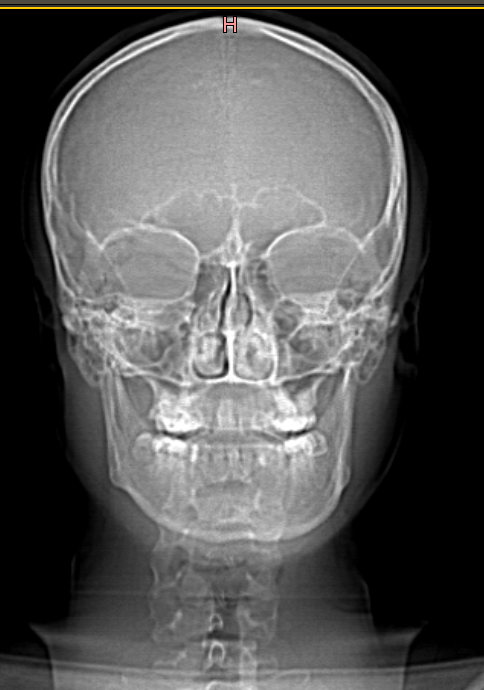

10.03.2023_19.18.47_REC